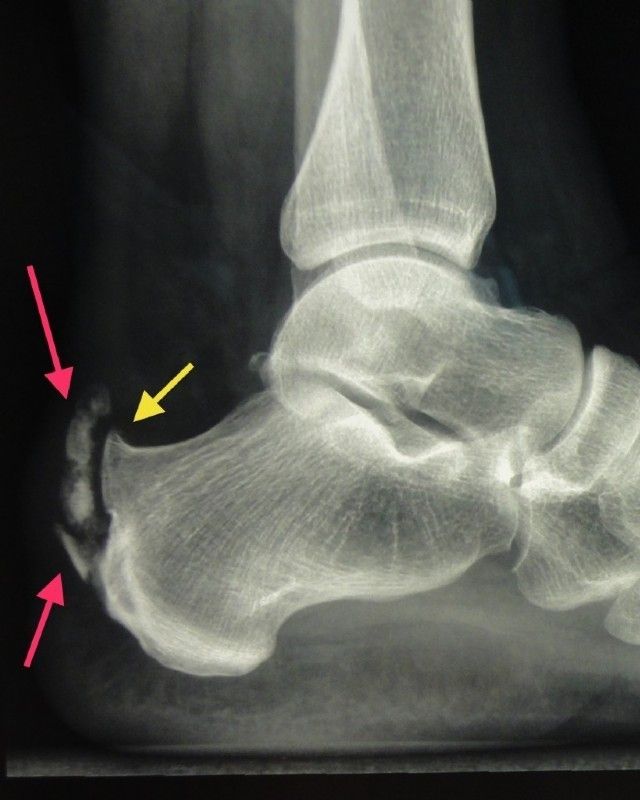

Left: Achilles tendon ossification- upper red arrow, sharp high heel bone – yellow arrow, additional lower calcaneal spur – lower red arrow

Middle: After removal of the ossification (blue arrow) and the high heel bone (yellow arrow)

Right: Reconstruction of the Achilles tendon insertion on the heel bone with a synthetic band (Lars band), which is routed through a bone channel in the heel bone (blue arrow) and then sewn to itself and the Achilles tendon (green arrow).